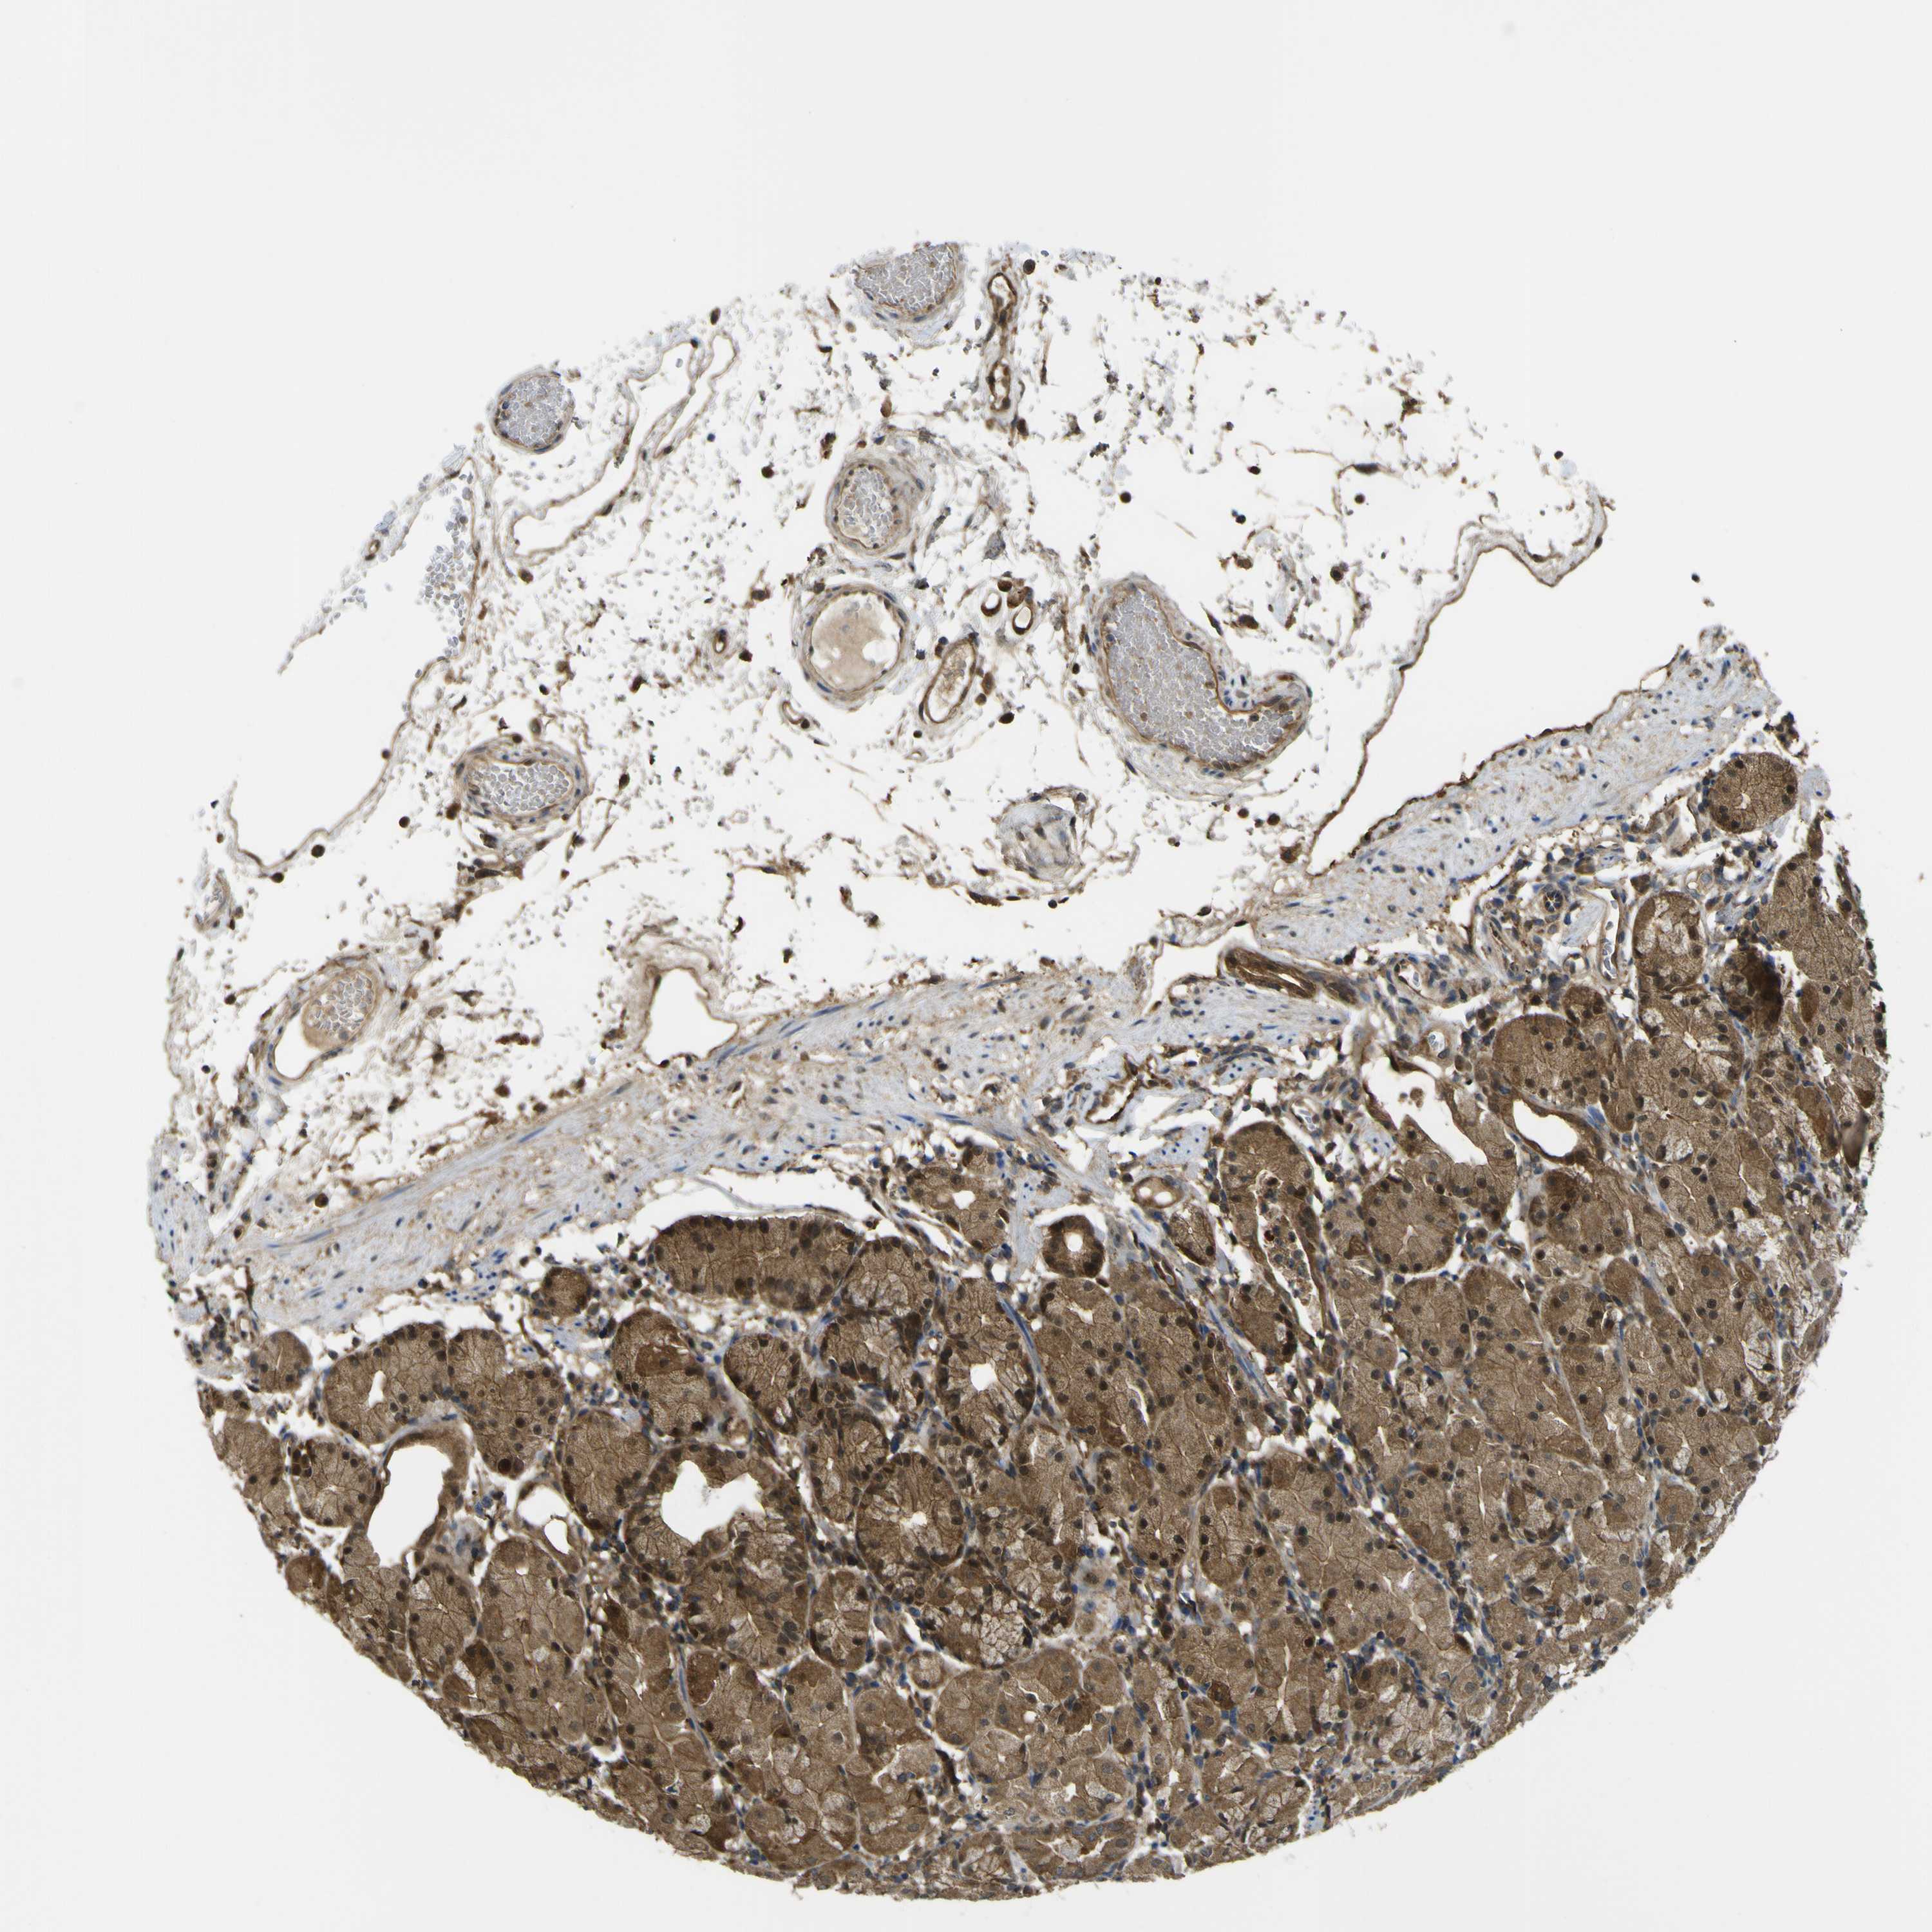

STOMACH 1 - Antibody stainingi

Antibody staining in the annotated cell types in the current human tissue is reported as not detected, low, medium, or high, based on conventional immunohistochemistry profiling in selected tissues. This score is based on the combination of the staining intensity and fraction of stained cells.

Each image is clickable and will lead to virtual microscopy that enables deeper exploration of all samples and also displays staining intensity scores, fraction scores and subcellular localization as well as patient and tissue information for each sample.

Antibody HPA026918Antibody CAB013274Antibody CAB018389

Glandular cells LowMediumMedium